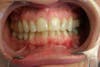

The photos enclosed with this article are of a patient we treated whose pain was, as she descibed it, " unbearable." I picked these photos to show you how tricky TMD van be. Her teeth are relatively straight and she has an acceptable bite to most untrained eyes.

But look closely: Her right side is lower than the left, and her teeth have a slanted angle. Now look at the after photo, teeth are longer, more vertical in place, and the right and left side of her upper jaw are parrallel horizontally. With several injectin of Botox and reconstruction of some teeth, she now is pain-free.